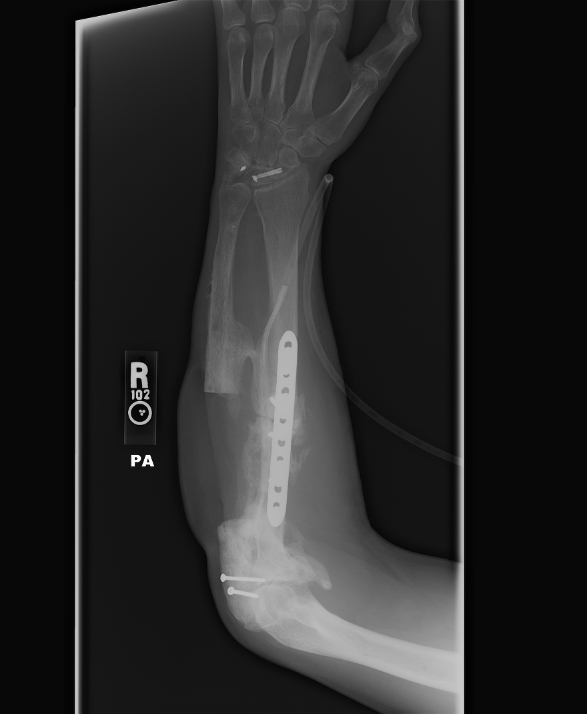

I have a couple of Robbie's latest X-rays. These show the missing 6 or 7 inches of bone in his arm........